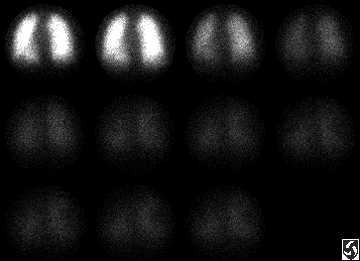

El Seguimiento Perfusion de Pulm�n Repasa

Sobre inicial perfusion pulm�n repasar, una fragmentario perfusion la falla que involucra el segmento anterior del l�bulo superior derecho es visible ( las flechas). Adem�s, un n�mero de subsegmental perfusion fallas est� presente en el l�bulo m�s inferior derecho, el l�bulo superior izquierdo, el lingula, y el l�bulo m�s inferior izquierdo.

Estas fallas se desigualan en el estudio de ventilaci�n.

Los hallazgos son uniformes con una probabilidad alta para la embolia pulmonar.

Un seguimiento perfusion el pulm�n repasa hecho una de semana despu�s del tratamiento con TPA muestra mejoramiento importante en los perfusion de ambos pulmones. El residuo peque�o perfusion abandona (las flechas) involucrando el �pice izquierdo y el l�bulo m�s inferior derecho permanece.